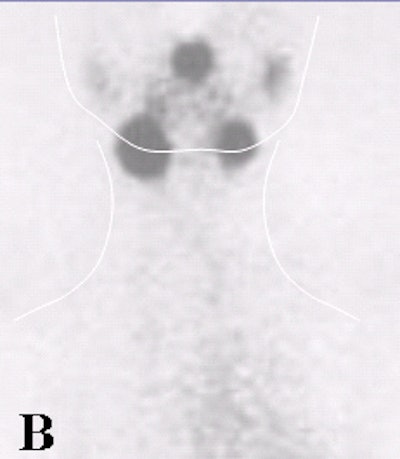

![]() |

| Fifty-three-year-old male with papillary carcinoma who underwent total thyroidectomy. First post-operative scan with 5 mCi 131I at 72 hours. Two foci of remnant metastases are seen. |

| Four weeks later, a scan with 100 mCi 131I at 72 hours was obtained. The stunned lesions failed to take up any of the therapy dose. |

| At one-year follow-up on 5 mCi 131I scan at 72 hours, the same two lesions are present. Images courtesy of Dr. Hee Myung Park. |